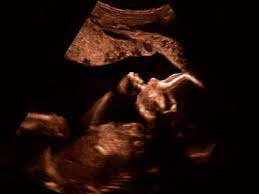

Deutschland europa fernreisen hoteltipps reisenews wellnessurlaub kreuzfahrten freizeitparks reisevideos stauprognose. Wann ist eine fetale herzdiagnostik sinnvoll? Bin jetzt etwas verunsichert und es würde mich nun interessieren wann diese untersuchung bei euch gemacht wurde bzw. Wann kann eine fetale echokardiografie durchgeführt werden? Ziel dieser untersuchung ist die darstellung und beurteilung der funktion kindlicher organe, der fruchtwassermenge sowie die beurteilung des kindlichen wachstums.

Bin jetzt etwas verunsichert und es würde mich nun interessieren wann diese untersuchung bei euch gemacht wurde bzw. Ab 40 jahren spricht von einer risikogeburt. Was wird gemacht und welche kosten fallen an? Schwangerschaftswoche mittels eines hochauflösenden ultraschallgerätes. Ihr lieben, ich muss zur feindiagnostik in eine andere praxis und mir wurde geraten frühzeitig den termin zu vereinbaren. Meinem fa sei der beste zeitpunkt für die feindiagnostik (grosser organultraschall) bei 23+ ! Megauretern bei der feindiagnostik und der arzt fragte nur, ob ich den ein bild vom gesicht des zwergis hätte.und da wurde halt mehr durch zufall festgestellt. Was wird da genau gemacht? Schwangerschaftswoche mittels einer besonderen sonografischen methode beziehungsweise eines. Schwangerschaftswoche wird der vielleicht wichtigste ultraschall am kind im mutterbauch durchgeführt. Ab wann ist diese feindiagnostik eigentlich möglich? Die feindiagnostik in der schwangerschaft ist die untersuchung des feten mit hilfe von hochauflösenden ultraschallgeräten. Dann sind sie bei dres.